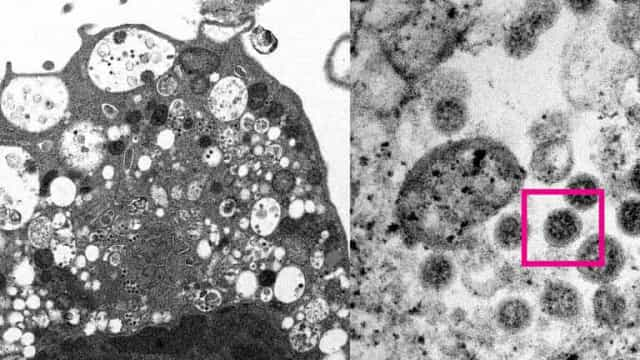

Leia maisSÃO PAULO, SP (FOLHAPRESS) – Dois cientistas da Universidade de Hong Kong divulgaram nesta terça-feira (8) as duas primeiras imagens da variante ômicron,